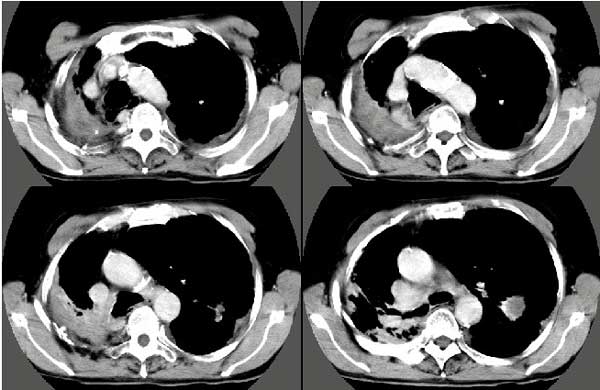

以下是引用扬仪在2005-5-12 20:46:40的发言:[br]右肺呈术后改变;双侧肺野散在分布斑片状、点状高密度病灶,(似可见“树芽征”);左上尖后段见斑团状高密度病灶(2个层面?),边缘毛糙,段性分布,与斜裂相邻,临近胸膜粘连;增强示病灶边缘强化,内呈水样密度;心影、纵隔右移,内可见4r淋巴结肿大。[br]意见:1、双肺继发性肺结核,左上为干酪病灶;[br] 2、矽肺合并感染;[br] 3、建议抗痨+抗炎。 [br]愚人之见,请高人指教!